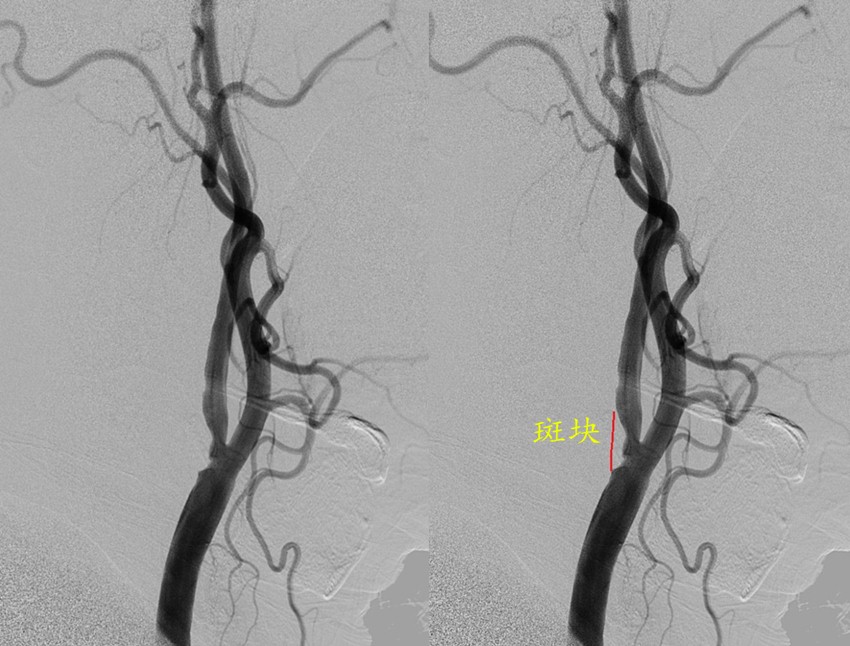

清华长庚医院7月16日电(通讯员  杨宇 吴巍巍)王老今年70岁,15年前曾有脑梗死,当时左侧肢体活动不利,目前无遗留症状,1周前体检超声发现右颈动脉狭窄,赶紧就诊清华长庚医院血管外科,医生发现王老的右侧颈内动脉起始端粥样硬化斑块形成、重度狭窄,超声造影检查及颈动脉斑块MRI分析均提示不稳定斑块,极易脱落导致脑梗死。吴巍巍主任团队经过仔细讨论分析病情,决定为王老实施颈动脉内膜剥脱手术,并决定术中联合神经内科医师予以经颅多普勒监测大脑中动脉血流,保证手术精准安全。经过术前仔细准备,血管外科吴巍巍主任、赵克强教授在麻醉科医师的保驾下为王老安全施行颈动脉内膜剥脱术,从颈动脉分叉处取出了一块长约3cm的淡黄色厚实斑块,斑块可见破碎出血,符合不稳定斑块的特征,避免了王老发生严重的脑梗塞。经过CCU团队与血管外科团队严密监护控制血压,王老在术后1周顺利康复出院。

颈动脉彩超检查能够做出初步判断,但其受检查技师操作经验及主观判断影响大。为了进一步指导手术治疗,还需要明确颈动脉狭窄部位、长度以及程度、斑块成分等详细信息。颈动脉血管造影(DSA)能准确检查出动脉狭窄的程度和范围,是诊断动脉病变的金标准。近年来,应用超声造影、CT血管增强(CTA)以及磁共振斑块分析(MRI)等技术,同样可以得到全面的动脉狭窄信息,通过三维建模从不同的角度显示血管结构,良好地识别不稳定斑块。